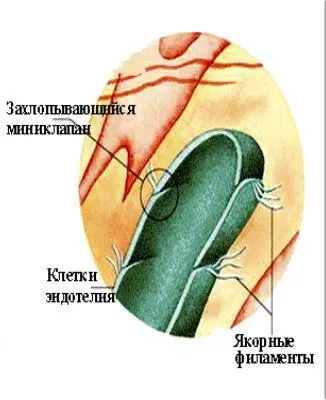

Структурные основы лимфообразования (схема): подвижные межэндотелиальные контакты лимфатических капилляров устроены и функционируют как внутристеночные клапаны с подвижной внутренней и фиксированной (якорными филаметами) наружной «створками»

Они организуют пассивный лимфоотток из лимфокапиллярной сети благодаря клапанам. Стенки межклапанного сегмента сближаются под давлением наружной манжетки (паравазальные ткани) и выдавливают лимфу из его полости в обоих направлениях. Дистальный (входной) клапан ограничивает обратный лимфоток: клапанные синусы (промежутки между клапанными заслонками и стенками сосуда в виде карманов, открытых проксимально) заполняются лимфой, под ее давлением створки клапана сближаются и он закрывается. Прямой лимфоток раздвигает створки проксимального (выходного) клапана, устремляясь в следующий межклапанный сегмент. Клапан относится к обоим смежным сегментам лимфатического посткапилляра: он разделяет их полости (автономные компартменты), но объединяет их стенки, обеспечивая целостность микрососуда. Около магистральной артериолы и магистральной (мышечной) венулы или в составе их пучков (контур «микрорайона» микроциркуляторного русла) лимфатический посткапилляр переходит в лимфатический сосуд I порядка.